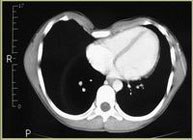

Les dades mèdiques del pacient, més l'exploració clínica realitzada per l'equip de cirurgia, juntament amb una anàlisi detallada de les imatges del TAC i les reconstruccions digitals en 3D de cada tòrax realitzades conjuntament amb l'equip d'enginyers de Ventura Medical Technologies, són la base per determinar si la tècnica Pectus Up està indicada i com cal procedir en cadascun dels pacients.

Pectus Excavatum Pectus Excavatum Asimétrico Índice de Asimetría 0.6 (+R/-L)(|AI|> 0.05 Asimétrico) Índice de Haller 4.5 (HI >3.5) Índice de Corrección 49.13% Rotación esternal 18.1 ° (a la derecha)

Informe d'avaluació del TAC d'un pacient enviada al cirurgià